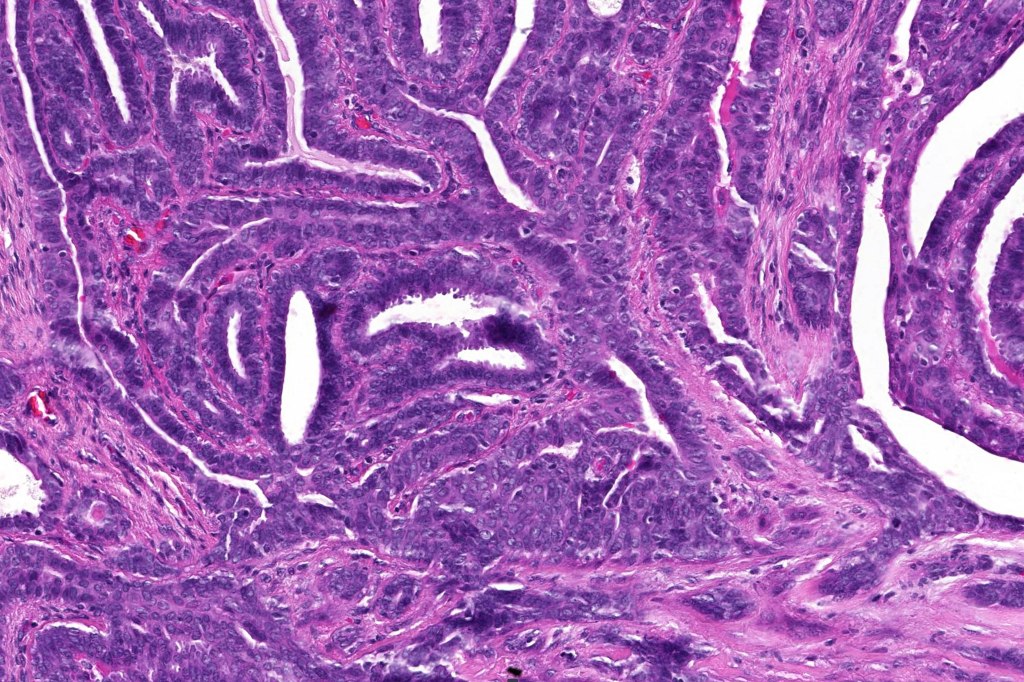

Histological features

•Circumscribed intradermal/lamina propria nodule

•Cystic or solid

•Papillae lined by myoepithelial cells with overlying epithelial cells with eosinophilic cytoplasm showing decapitation secretion

•+/- Oxyphil metaplasia

•Cribriform pattern sometimes evident

•Solid pattern